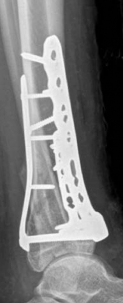

Fig 2.2-6a–b Immediate postoperative x-rays showing restoration of the ankle mortise and distal tibia alignment through anatomical and stable fracture fixation.

1. AP view.

2. Lateral view.